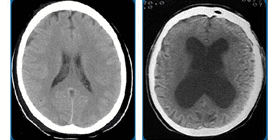

About Hydrocephalus

What is Hydrocephalus? Hydrocephalus is a chronic, neurological condition caused by an abnormal accumulation of cerebrospinal fluid (CSF) within the cavities (ventricles) of the brain. Hydrocephalus happens when there is an imbalance between the amount...

Normal Pressure Hydrocephalus (NPH)

What is Normal Pressure Hydrocephalus (NPH)? Normal pressure hydrocephalus (NPH) is when there is a build-up of cerebrospinal fluid (CSF) in an area in the center of the brain called (ventricles). This causes the ventricles...